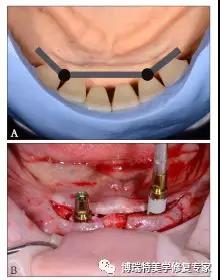

3)制定治疗计划:黏膜支持式总义齿修复上颌无牙颌;种植体-杆卡固位覆盖义齿修复下颌无牙颌。根据人工牙的排列设计杆的位置,使杆位于牙槽嵴与人工牙间,并设计种植位点(图3A);运用双侧游离端短悬臂,增加义齿稳定与固位。依诊断排牙翻制种植手术导板。

4)种植手术:依据种植手术导板,在下颌双侧侧切牙与尖牙之间的位点各植入1枚3.8 mm×11 mm种植体(XIVE,Friadent公司,德国),植入扭矩25 N·cm(图3B)。

图3 种植位点及手术。A:根据人工牙与牙槽嵴顶水平关系设计杆卡及种植位点,使杆位于牙槽嵴顶与人工牙之间;B:按照设计位点植入2枚种植体。